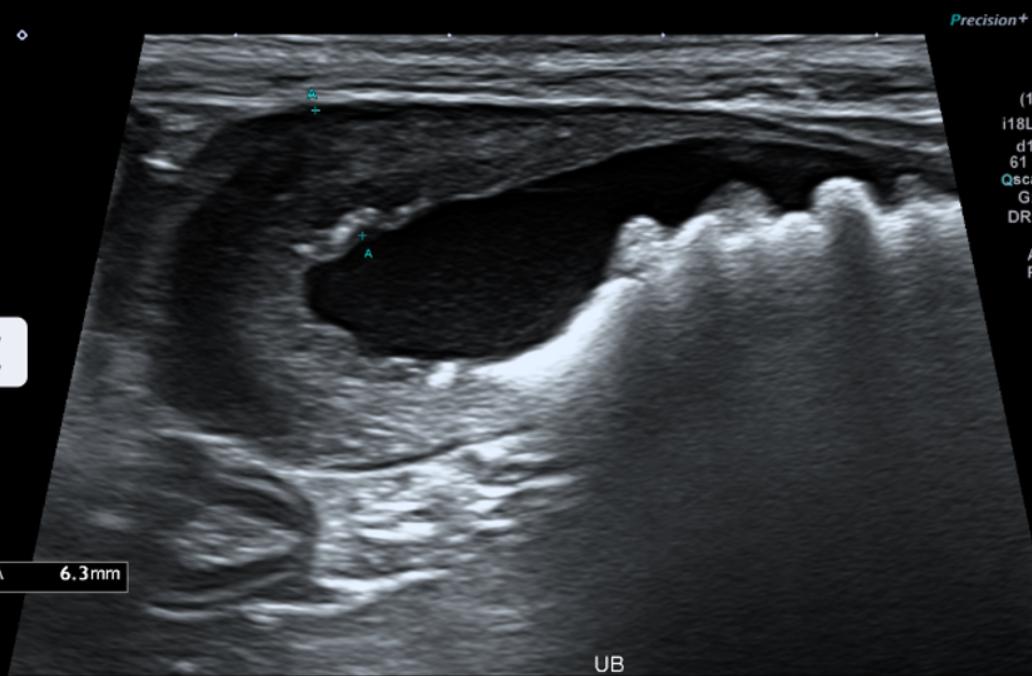

Abdominal ultrasound(복부 초음파)

bladder wall(방광벽)이 두꺼워져 있어 chronic cystitis(만성 방광염)을 의심할 수 있는 소견

bladder 안에 다수의 결석(cystolith)이 확인되었고, urethra(요도) 방향으로도 여러 개의 결석이 내려가 있는 상태가 확인되었습니다.

초음파에서 bladder 내 다수의 방광결석,urethra 쪽으로 내려간 결석들,bladder wall 비후(방광염 소견)가 동시에 확인되었습니다.